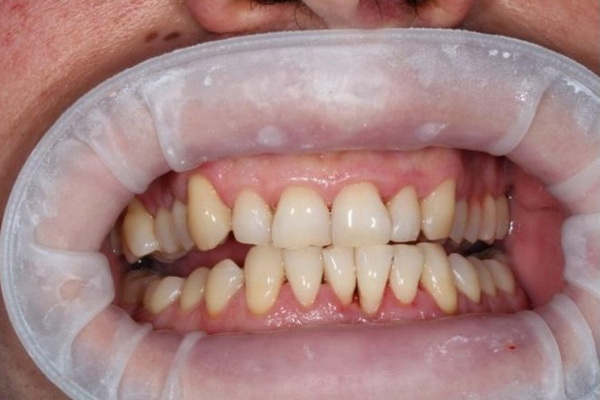

Такий був вигляд ясен пацієнта після лікування: ясна блідо-рожевого (природнього) кольору, не набряклі. Після видалення зубного каменю оголились поверхні коренів зубів: запалення в тканинах навколо зуба спричиняє руйнування кісткової тканини в якій знаходяться зуби, що призводить до опускання ясен на нижній щелепі та їх підйом на верхній щелепі.